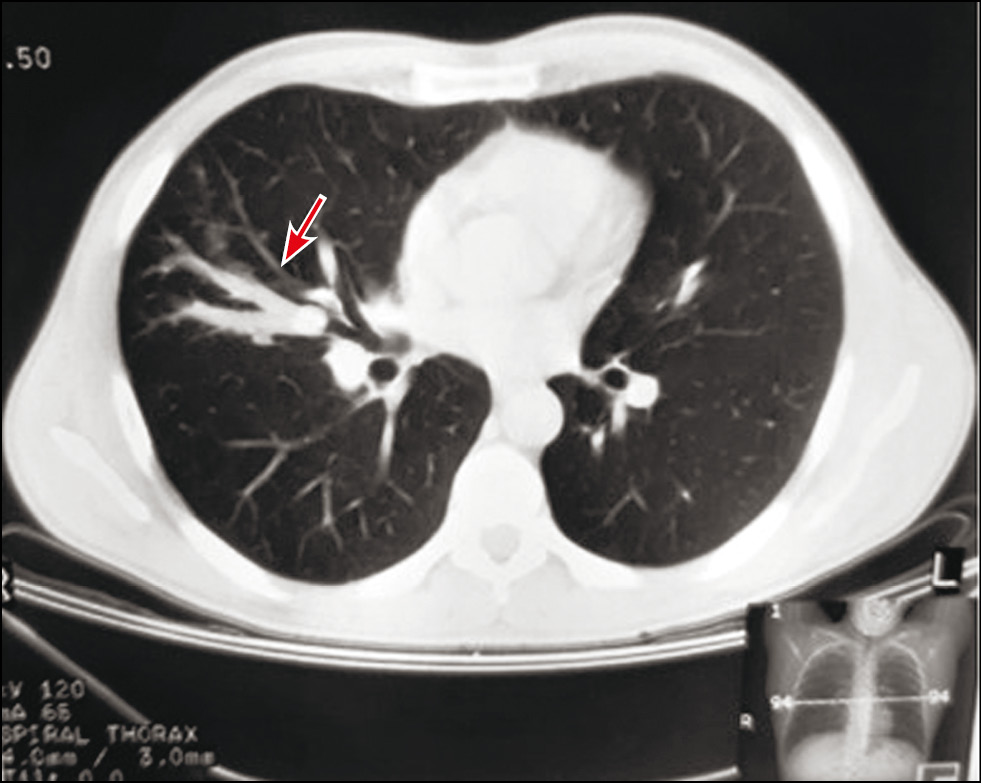

Fig. 1. Patient, 56 years old, chest x-ray: a - at the initial examination at the age of 41 in the middle section of the right lung, a seal area of a branched tubular structure is determined (arrow); b - 15 years later, there was an increase in the size of the bronchocele (arrow) and the appearance of a rounded formation in the medial regions bronchocele (arrowhead).

The history assessment revealed that he was examined for pneumonia 15 years ago. Despite the positive dynamics based on clinical studies, during the course of antibiotic therapy, radiological findings did not correspond to the typical course of regression of infiltrative lungs changes in pneumonia. X-ray imaging of the chest revealed an area of induration of a tubular branched structure in the middle section of the right lung (Fig. 1, a). Additional studies, including computed tomography of the chest with intravenous contrast enhancement, fibrobronchoscopy, and immunological and bacteriological studies, did not detect tuberculosis or an oncological process. Computed tomography data were presented as selective scans on a film carrier, which revealed a local, single branched structure with smooth, clear contours, located along the subsegmental bronchi of the middle lobe of the right lung (finger in glove sign), with homogeneous contents (Fig. 2), so the patient was diagnosed with bronchogenic retention cyst (bronchocele) on the middle lobe of the right lung. Subsequently, follow-up studies were performed annually by X-ray examination of the chest, and stable changes were observed.

Fig. 2. The same patient. Selective computer scan tomography of the chest cavity organs: uniform V-shaped structure in the middle lobe of the right lung with clear contours (arrow).

In the present case, although the cause of the bronchocele development was not established in the initial comprehensive examination, retrospective assessment of computed tomography data presented on a film carrier revealed the presence of a lesion at the base of the bronchocele (Fig. 2). With its extrabronchial location, changes during fibrobronchoscopy may not be detected.